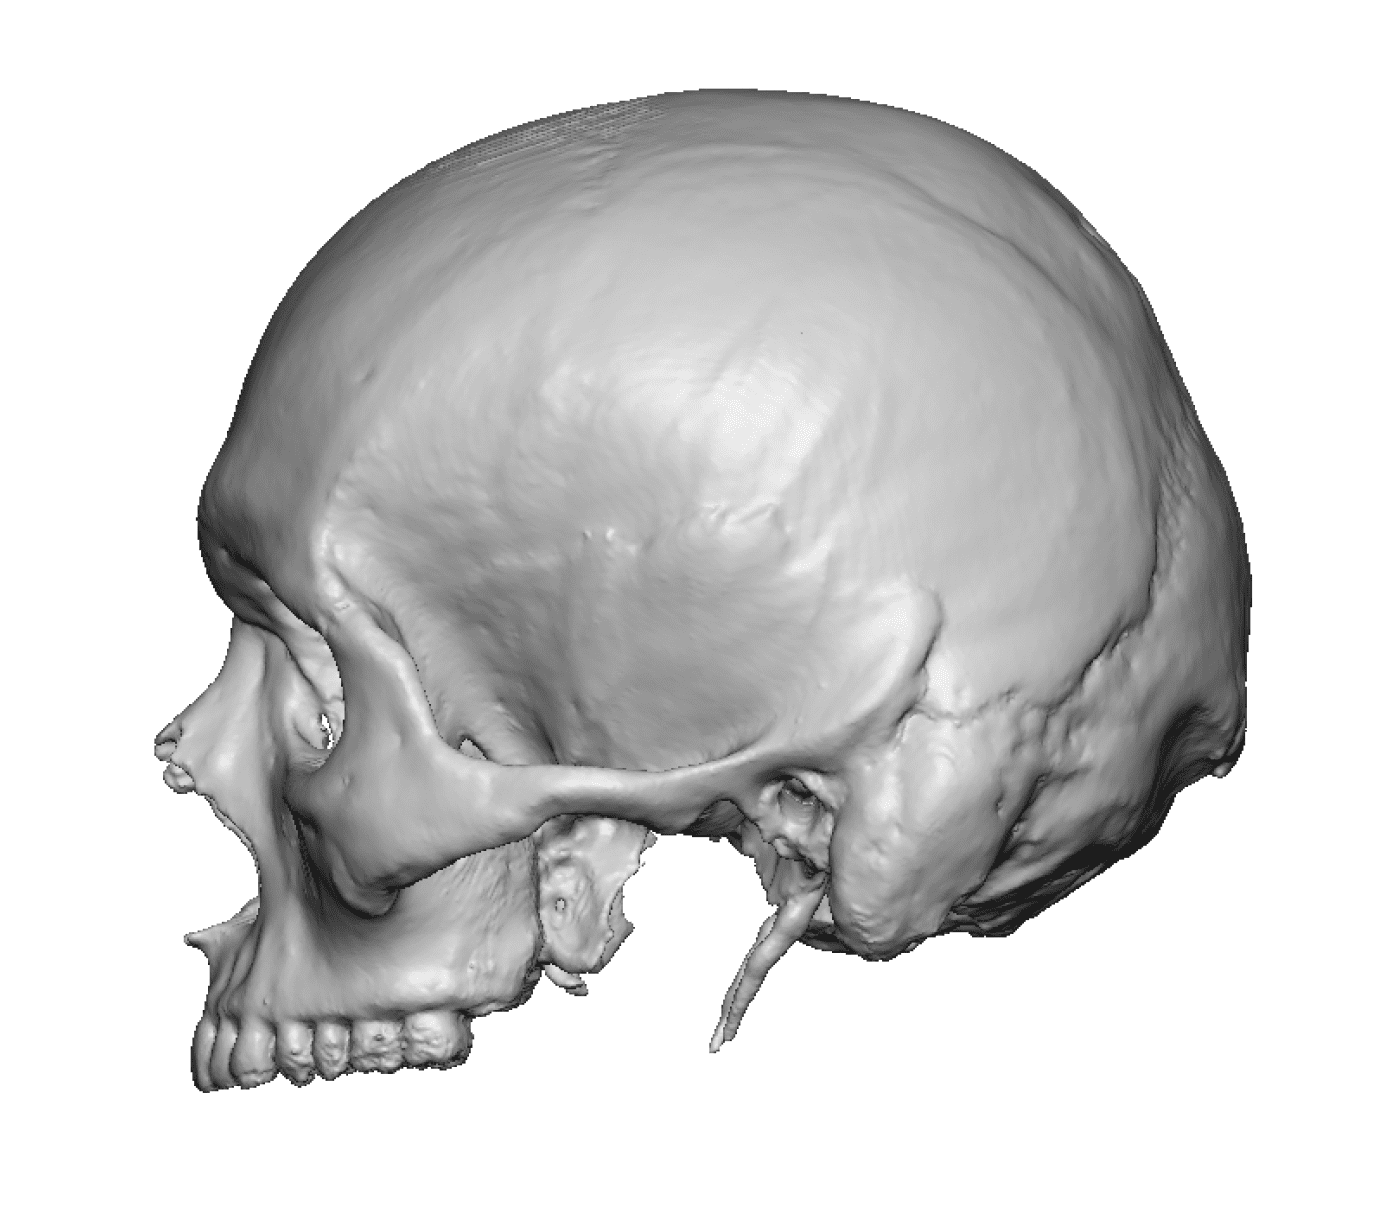

Severe narrowing skull deformity from prior sagittal craniosynostosis repair as an adult.

Complete replacement of entire skull by a custom implant with temporal fat injections.

Severe narrowing skull deformity from prior sagittal craniosynostosis repair as an adult.

Complete replacement of entire skull by a custom implant with temporal fat injections.